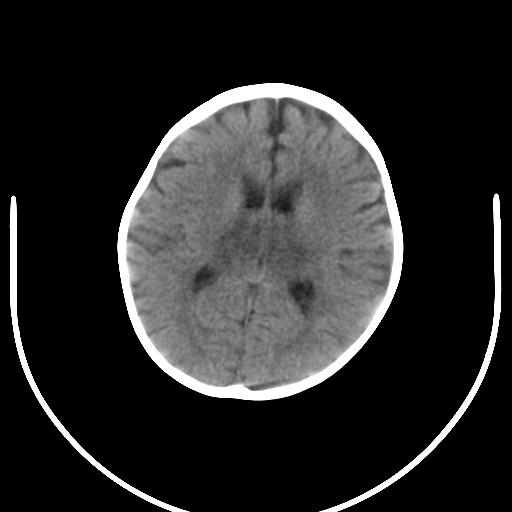

8月患儿,咳嗽、发热1周,5天前头部有外伤史,阵发性肌张力增高。前囟平,张力不高。

1.环池.脚间池浑浊,双基底节区近中线对称性片状低密度影,考虑脑炎.建议腰穿.

双侧背侧丘脑对称性密度减低,有发热咳嗽症状,考虑1感染2缺氧或体内代谢终产物中毒

双侧背侧丘脑对称性密度减低,有发热咳嗽症状,考虑1感染2缺氧或体内代谢终产物中毒

右侧外囊见点片状低密度灶,双测背侧丘脑对称行密度减低,结合病史首先考虑感染性病变,其次外伤性脑梗塞建议mri检查。

直接征象:双侧丘脑对称性密度减低;

除了要考虑到感染性疾病外还应考虑到脑变性性疾病的可能;

暂时不考虑肿瘤性病变和中毒性病变;

双侧背侧丘脑对称性密度减低,有发热咳嗽症状,考虑1感染2缺氧或体内代谢终产物中毒3.外伤性脑梗塞也得考虑。肿瘤不考虑。建议mri检查。

1皮层区脑萎缩2丘脑区低密度考虑脑炎。

患儿有明显的外伤史,首先应考虑脑梗塞。而缺氧性改变只能是并发症。